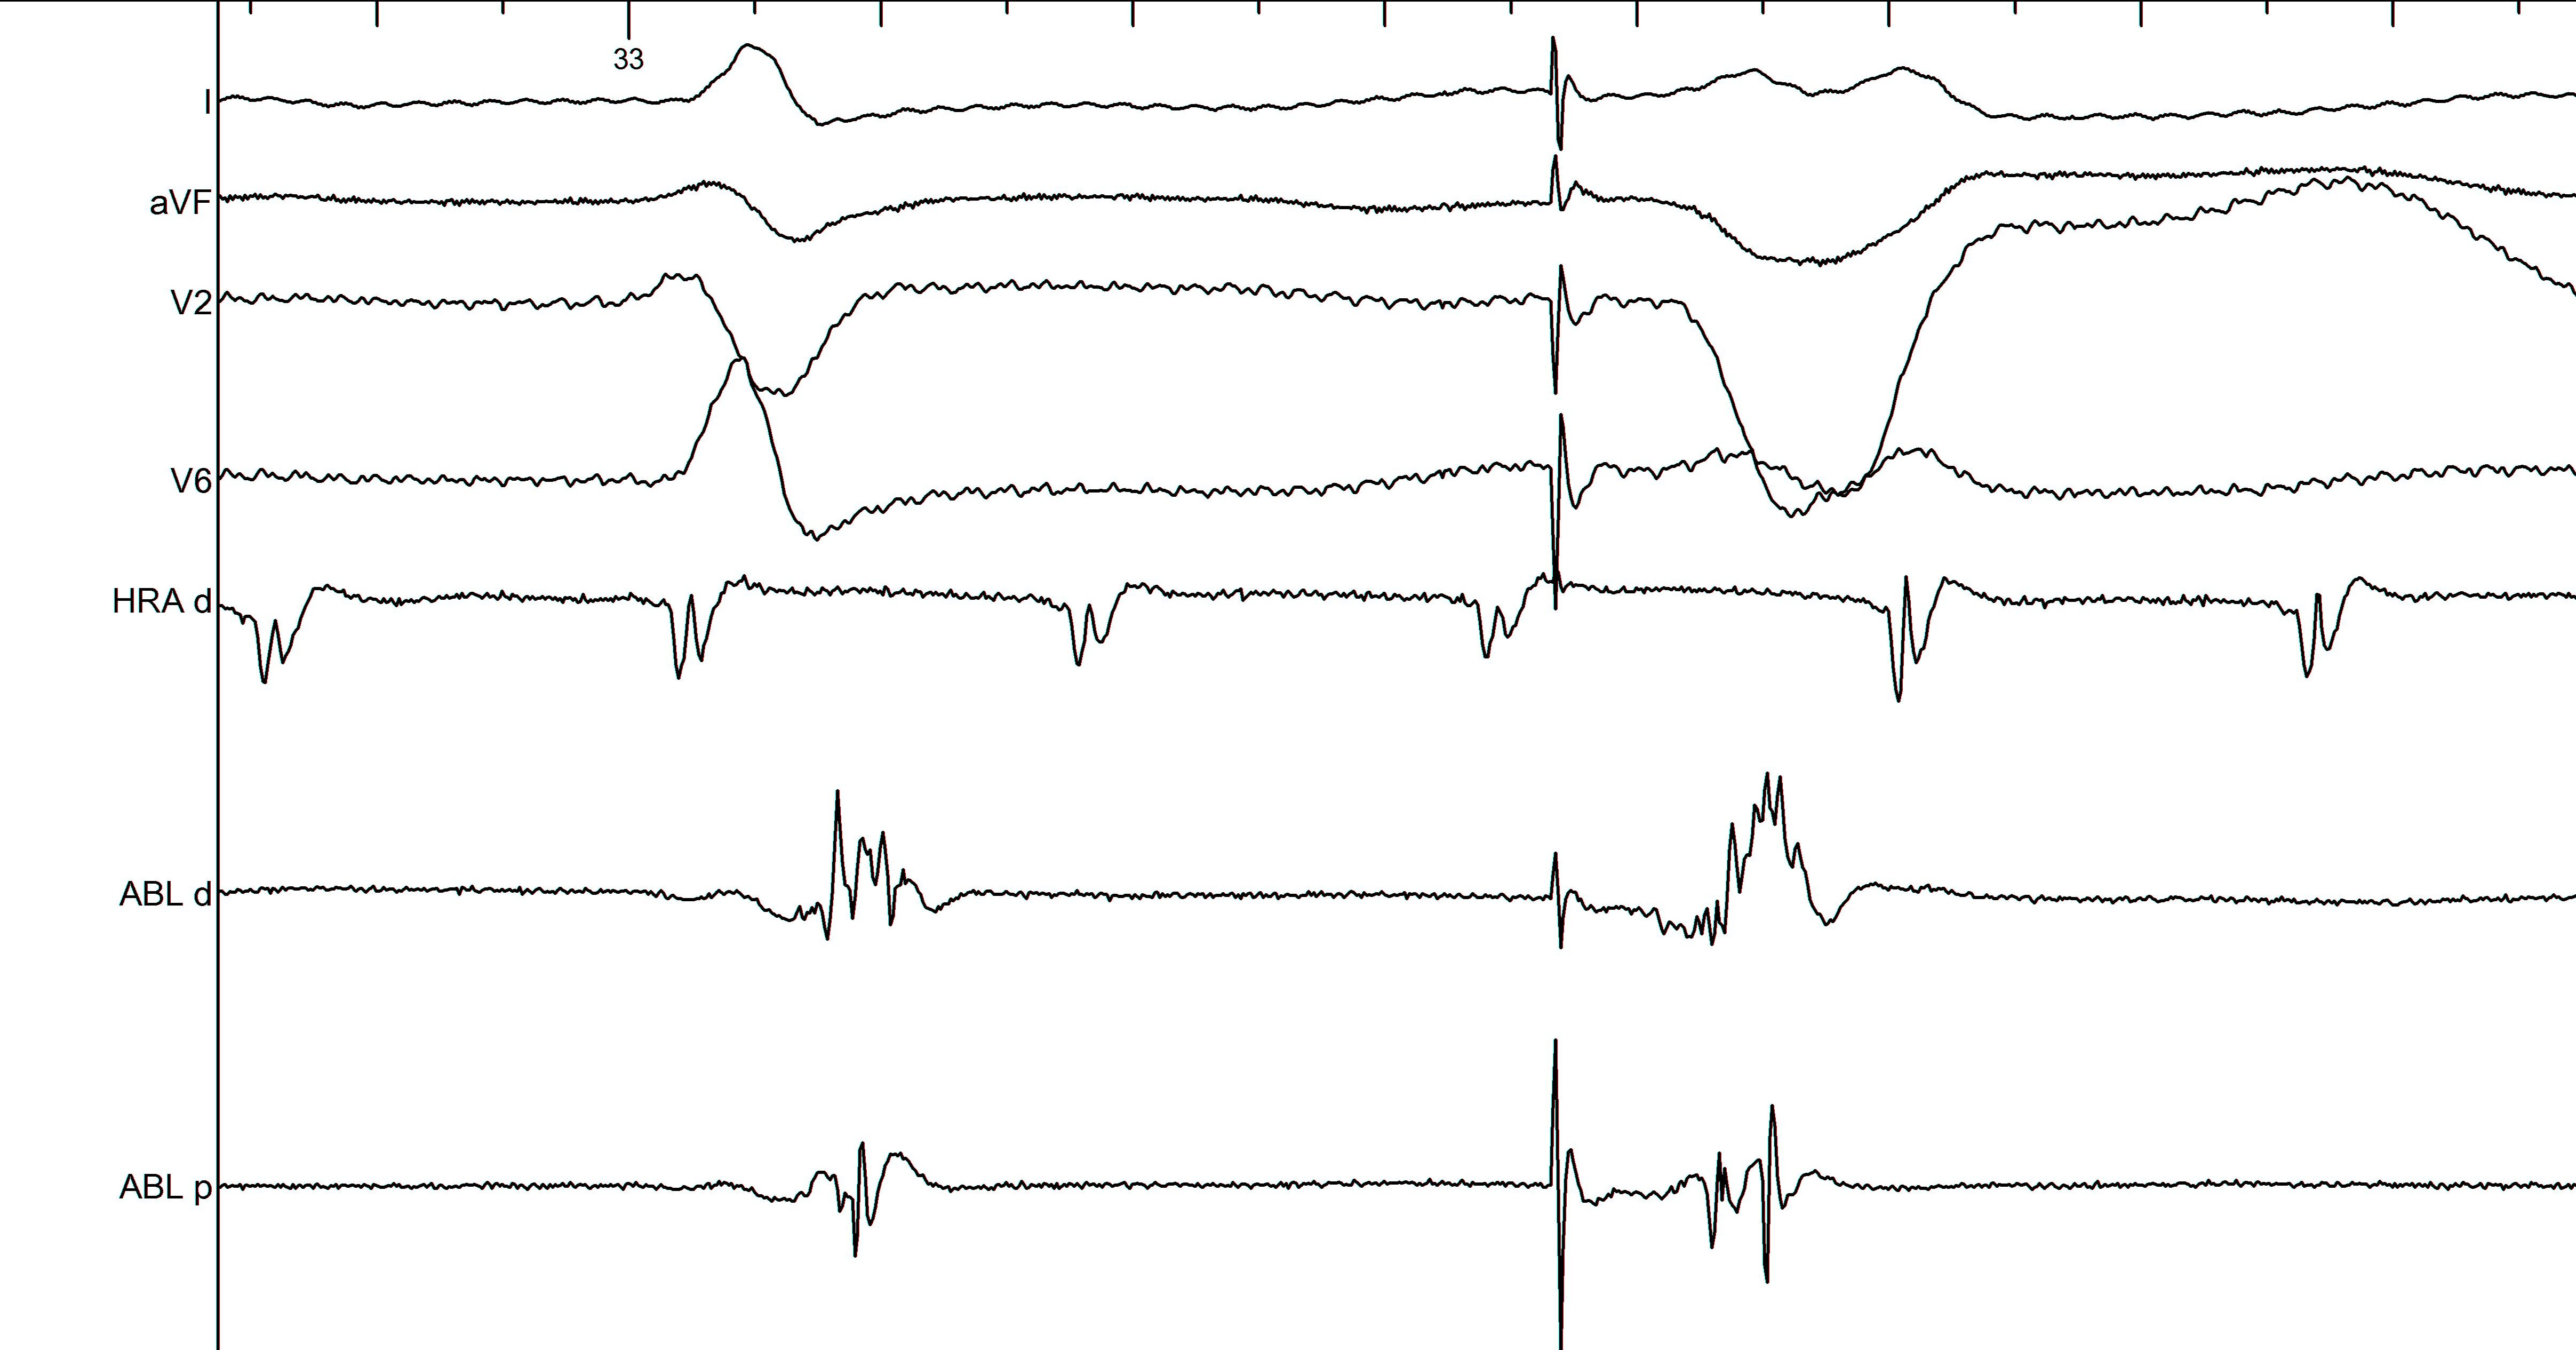

Delayed potentials

Principle

• Bundles of surviving muscle fibers within scar

• Slow conduction because of poor coupling

• Far field early signal and near field late signal

Late potential - How late is late ?

• EGM extending beyond surface QRS (1)

• Remnant from SAECG

• More likely to identify in late activated regions

• 2 or more components, separated by isoelectric segment >50 ms (sinus) or 150 ms (RV pacing) (2)

• High frequency signals distinct from far-field electrogram (3)

Pacing from abnormal sites

• Non capture to identify scar

• Latency - correlates with late potential - may be discordant in 40% (1)

• Differentiate far field from near field (1)

• Paced morphology

• Putative isthmus (2)